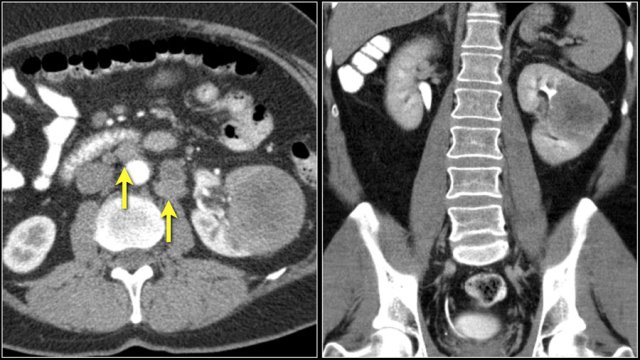

A typical feature of clear cell carcinoma is strong enhancement in the corticomedullary phase.

This can be difficult to assess when the lesion is small and located in the renal cortex, which also enhances strongly.

The nephrogenic phase is therefore the most sensitive phase for the detection of these lesions, as the renal parenchyma enhances homogeneously and more intensely than the tumor (figure).

The corticomedullary phase 25-40 sec post injection is strongly recommended. It helps to differentiate tumor from pseudotumor and to assess enhancement of a lesion.

In this phase however a tumor located in the renal medulla can have the same attenuation as the surrounding parenchyma (figure).

Therefore the nephrogenic phase (±100 sec post injection) is the most important phase for the detection of a tumor.